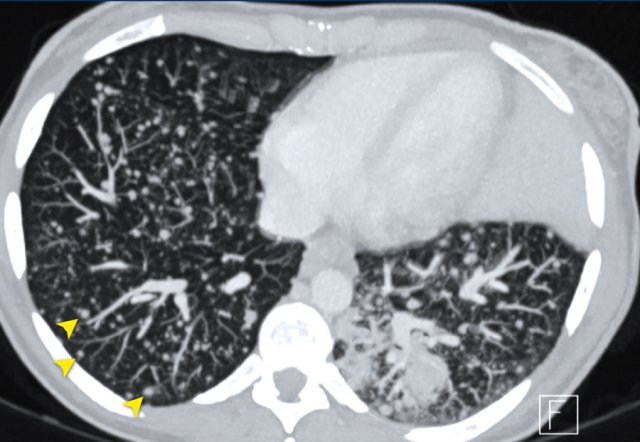

The CT images are of a 50-year-old female with bone metastases of a breast carcinoma.

At baseline (a), there is an osteolytic lesion in a thoracic vertebral body (arrow).

After chemotherapy, the thoracic osseous lesion has not changed in size, but has become completely osteoblastic (arrow in b), representing a good response.

In the lumbar vertebra no visible metastases were seen in the baseline scan (c).

The ‘new’ sclerotic lesions in the lumbar vertebra (arrowheads in d), are considered to be small osteolytic metastases that the baseline CT failed to identify.

They became visible due to the osteoblastic reaction.